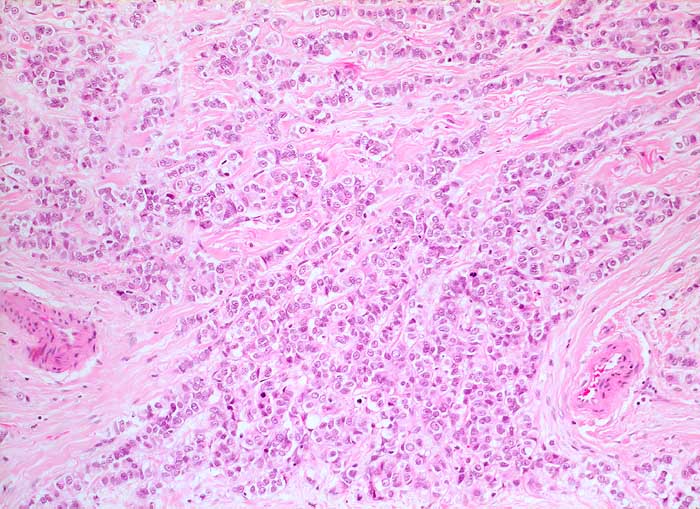

PathoPic – image database / PathoPic ID 5905 - invasiv lobuläres Mammakarzinom

invasiv lobuläres Mammakarzinom

maligner Tumor

Mamma

Die monomorphen Tumorzellen sind in Einerreihen angeordnet. Zwischen den Zellreihen desmoplastisches Stroma.

Metastasierendes Mammakarzinom

Histologie

200